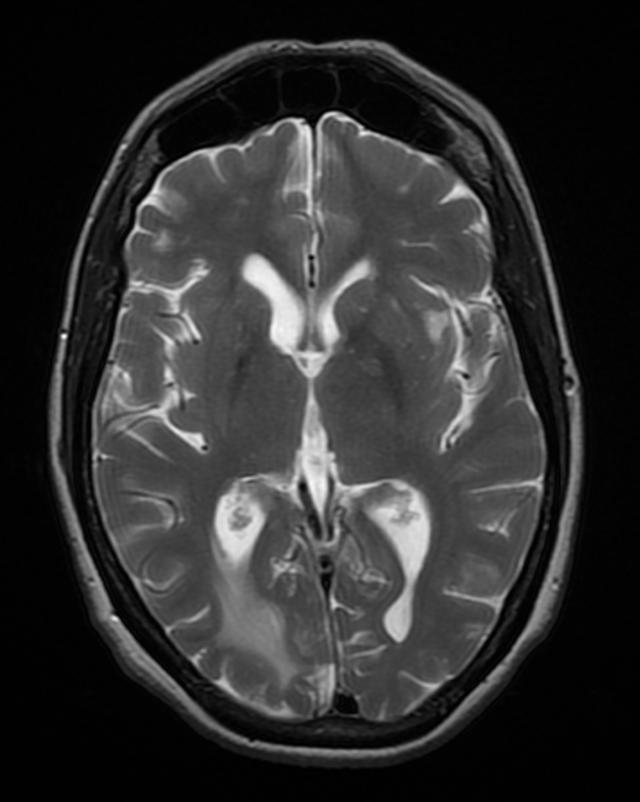

Brain toxoplasmosis

Right occipital lobe toxoplasmosis in a patient with AIDS

Source: Wikimedia commons, Jmarchn

https://upload.wikimedia.org/wikipedia/commons/f/f3/BrainToxoplasmosis_MRI_4_11.png

- T. gondii encephalitis presents as fever, headache, confusion, seizure, and focal motor findings with ring-enhancing lesions [Fig 4]. Patients with encephalitis may present with a non-focal, nonspecific illness, headache, and psychiatric symptoms.

- Imaging for TE is contrast-enhanced CT or MRI that shows multiple ring-enhancing lesions with surrounding edema in the gray matter of the cortex or basal ganglia.

- Occasionally, TE can present as a single lesion.

- Multifocal lesions on contrast-enhanced brain CT or MRI, especially in the basal ganglia.